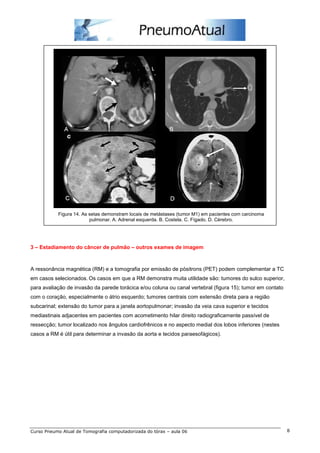

Figura 14. As setas demonstram locais de metástases (tumor M1) em pacientes com carcinoma

pulmonar. A. Adrenal esquerda. B. Costela. C. Fígado. D. Cérebro.

3 – Estadiamento do câncer de pulmão – outros exames de imagem

A ressonância magnética (RM) e a tomografia por emissão de pósitrons (PET) podem complementar a TC

em casos selecionados. Os casos em que a RM demonstra muita utilidade são: tumores do sulco superior,

para avaliação de invasão da parede torácica e/ou coluna ou canal vertebral (figura 15); tumor em contato

com o coração, especialmente o átrio esquerdo; tumores centrais com extensão direta para a região

subcarinal; extensão do tumor para a janela aortopulmonar; invasão da veia cava superior e tecidos

mediastinais adjacentes em pacientes com acometimento hilar direito radiograficamente passível de

ressecção; tumor localizado nos ângulos cardiofrênicos e no aspecto medial dos lobos inferiores (nestes

casos a RM é útil para determinar a invasão da aorta e tecidos paraesofágicos).